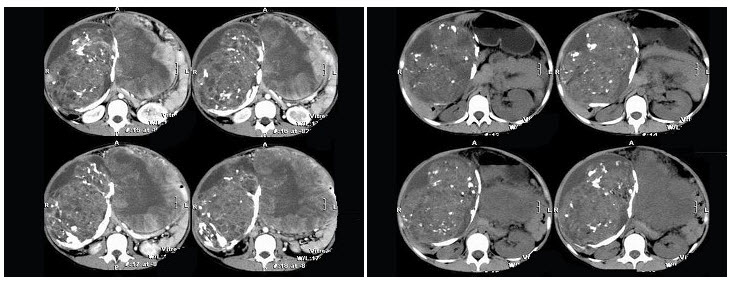

7、单项选择题

男,65岁,腋下触及肿大包块,全身浅表淋巴结肿大,结合所示图像,最可能的诊断是()

A.双侧肾上腺腺瘤

B.双侧肾上腺增生

C.双侧肾上腺淋巴瘤

D.双侧肾上腺转移癌

E.肾上腺癌